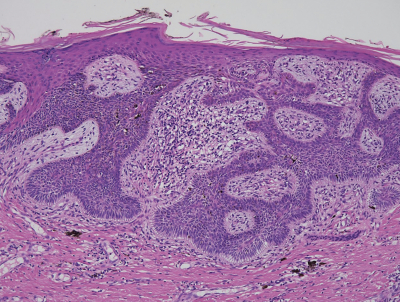

右肩甲部に約 2 cm の境界明瞭で平坦な淡褐色結節を認める。血液所見と血液生化学所見とに異常を認めない。胸腹部造影 CTで明らかな転移を認めない。生検で病理診断を行った後、結節を辺縁から 5 mm 離して切除した。術前の右肩甲部の写真と摘出組織の H-E 染色標本とを別に示す。H-E 染色標本で切除断端に病変はなかった。